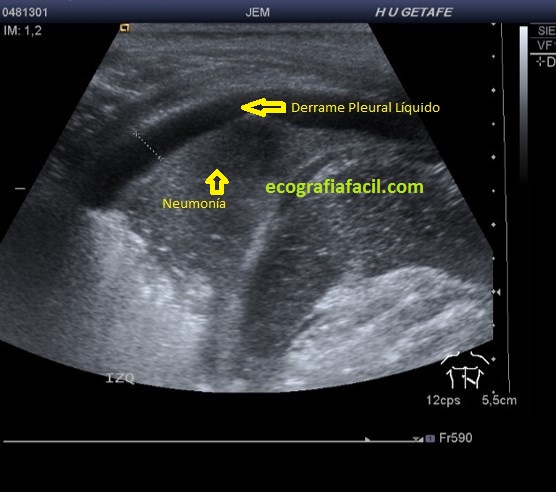

No siempre vemos una cámara líquida, también podemos ver diferentes tipos de formas de «agua», como la sangre o el moco y el pus de un proceso neumónico y como todas esas densidades se diferencia maravillosamente con ecografía.Esta imagen superior es un ejemplo perfecto.

We do not always see a liquid chamber, we can also see different types of «water» forms, like blood or mucus and pus from a pneumonic process and like all those densities it differs beautifully with ultrasound. This superior image is a perfect example.